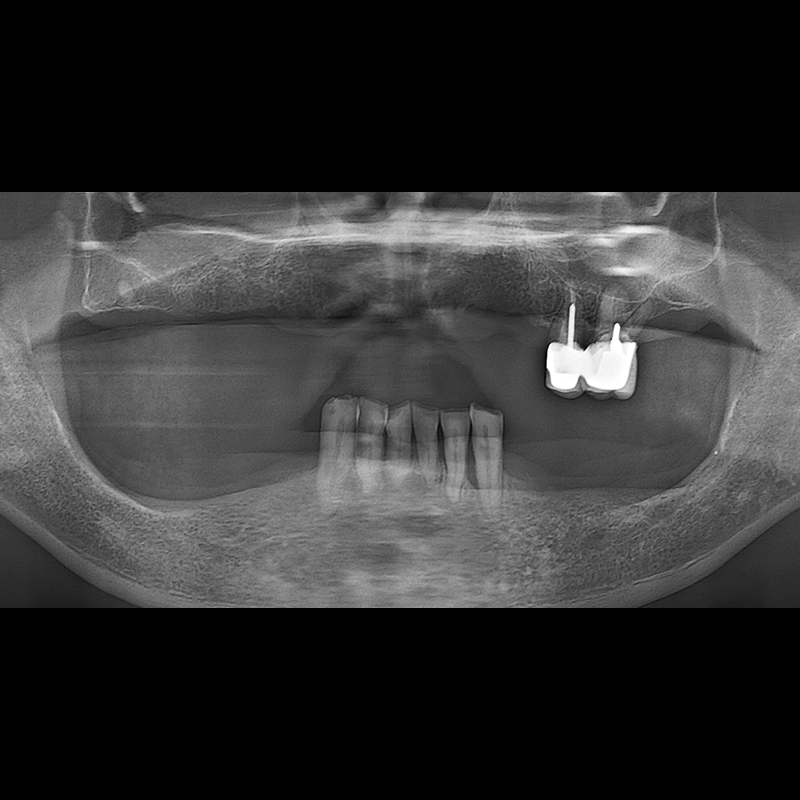

IMPLANT

BEFORE AFTER

种植牙前后的照片 2025.05.30

在缺失的牙齿部分和难以挽救的牙齿位置植入了种植牙。